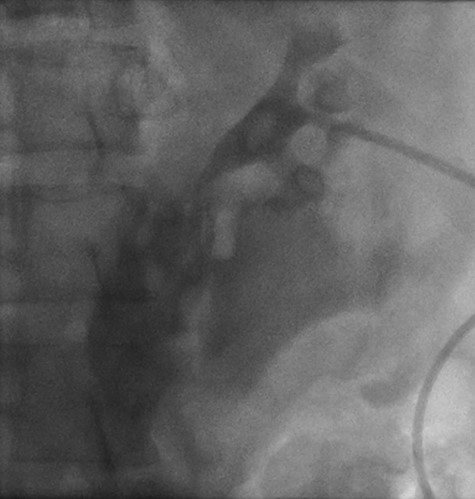

Left retrograde cystoscopy exhibiting extravasation of contrast.

Cystoscopy with retrograde pyelogram was performed by the urology team and this showed total disruption of the UPJ bilaterally with extravasation of contrast (Figs 3 and 4). She underwent bilateral interventional radiology nephrostomy tube placement. The definitive repair was planned for after pregnancy, but she required tube changes every 6 weeks. There was no fetal distress during her stay. She recovered well and was discharged after 5 days.